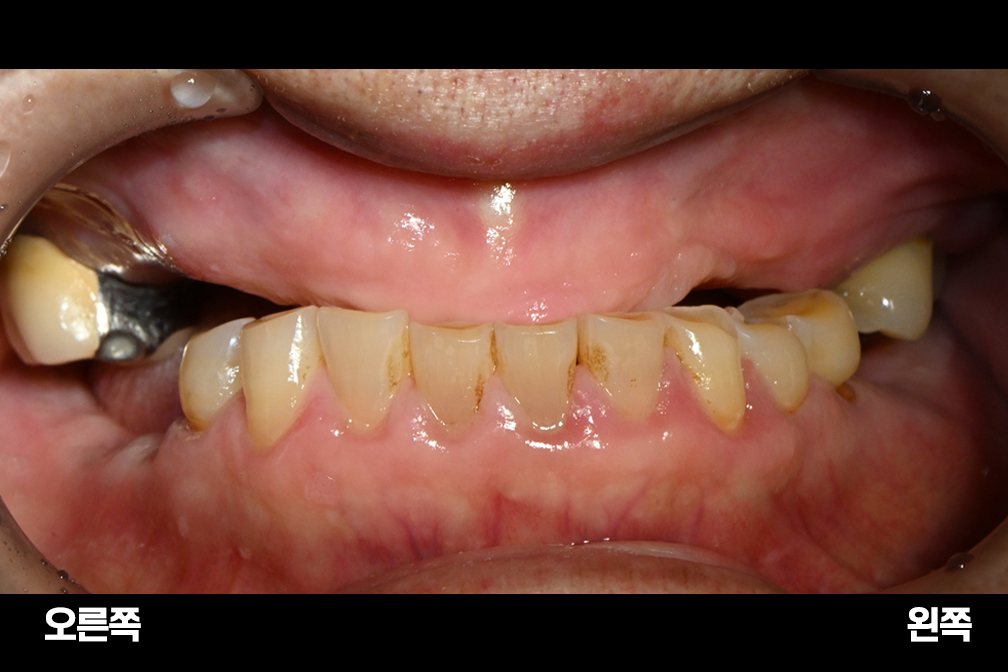

부분 틀니

Before 2026년 1월 12일

After 2026년 2월 21일